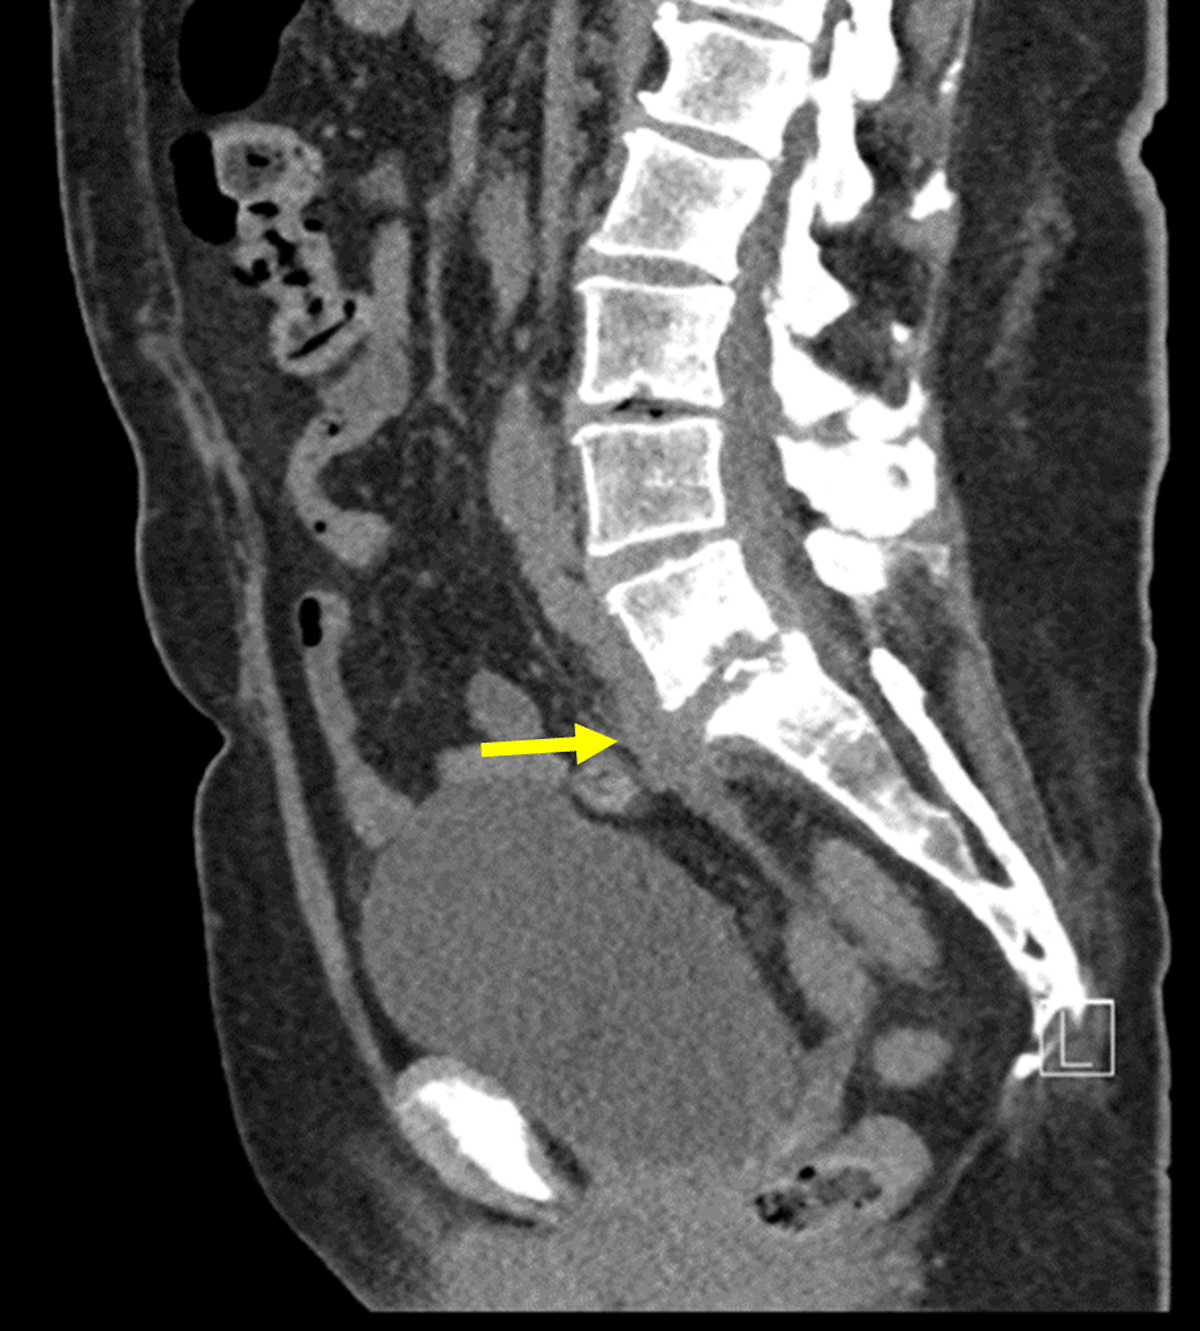

Figure 9

Sagittal contrast CT: Contrast CT-scan showing spondylodiscitis of L5-S1, with infiltration into the soft tissue surrounding S1. Additionally, a 9.7cm fistula can be seen, starting at the intervertebral disk of L5-S1 (yellow arrow) to the vagina.